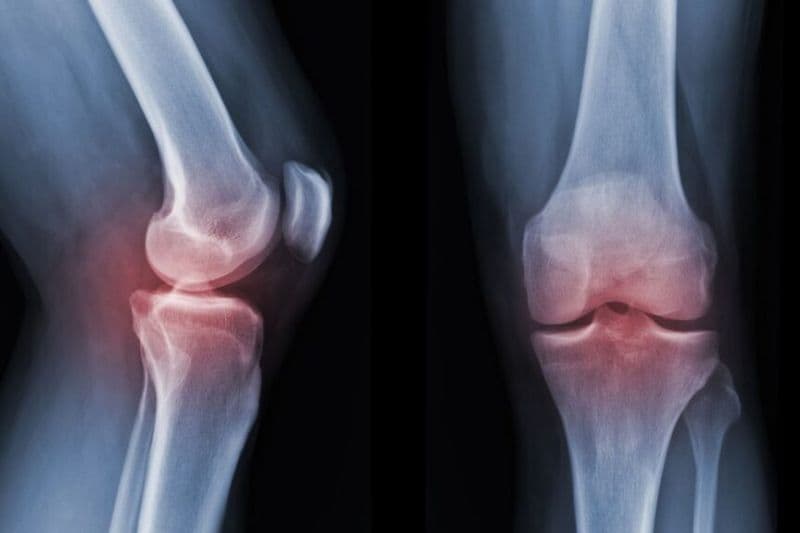

Theo Tiến sĩ, Bác sĩ Nguyễn Thị Ngọc – Chuyên gia Cơ xương khớp của Thu Cúc TCI, ở giai đoạn đầu của thoái hóa, các gai xương thường nhỏ, trên phim chụp X-quang chưa thấy biến đổi nhiều. Tuy nhiên theo tiến triển của thoái hóa qua các giai đoạn, các gai này có thể lớn dần, gây sưng, đau và ảnh hưởng đến vận động.